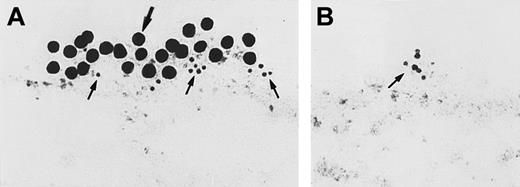

Investigations next proceeded to determine the amount of CK1 antigen expressed on HUVECs. An iodinated anti-RRY18 F(ab′)2was prepared for direct cell-binding studies (Figure4). When the iodinated F(ab′)2 was incubated with HUVECs, there was a plateau in binding at about 200 minutes (Figure 4). At that time, there was about 12 ng iodinated F(ab′)2 specifically bound per 106 HUVECs. This result calculated to be about 7.2 × 104 molecules of anti-RRY18 CK1 epitope per cell. Further investigations were performed to determine if CK1 antigen was on the membrane of HUVECs in suspension as determined by flow cytometry (Figure 5). Using flow cytometry, epitopes to CK1 were detected on HUVEC membranes using anti-GPV20 and anti-RRY184,5 (Figure 5). Additional studies were performed to determine if the other HK-binding proteins, uPAR and gC1qR, were present on HUVEC membranes. The uPAR was identified on HUVECs by flow cytometry (Figure 5). Moreover, unlike previous studies,6-8 gC1qR antigen was also expressed on the membrane of soluble HUVECs as seen on flow cytometry (Figure5). Confirmation that gC1qR antigen was expressed on the membrane of endothelial cells was performed by immunoelectron microscopy (Figure6). Using monoclonal antibody clone 74.5.2, gC1qR antigen was seen in clusters on the external membrane of EA.hy926 cells by immunoelectron microscopy using 10 nm immunogold (Figure 6).

Immunoelectron microscopy for gC1qR antigen on nonpermeabilized EA.hy926 endothelial cells.

Cell suspensions were fixed with PLPG and incubated with anti-gC1qR or nonimmune mouse IgG. (A) The bound anti-gC1qR antibodies were visualized by an immunogold procedure as indicated in “Materials and methods.” Clusters of 10-nm gold particles, indicating the presence of bound anti-gC1qR, are seen segmentally on the endothelial plasma membrane. (B) Incubation of nonimmune IgG with the cells. The figure is a representative experiment of 2.